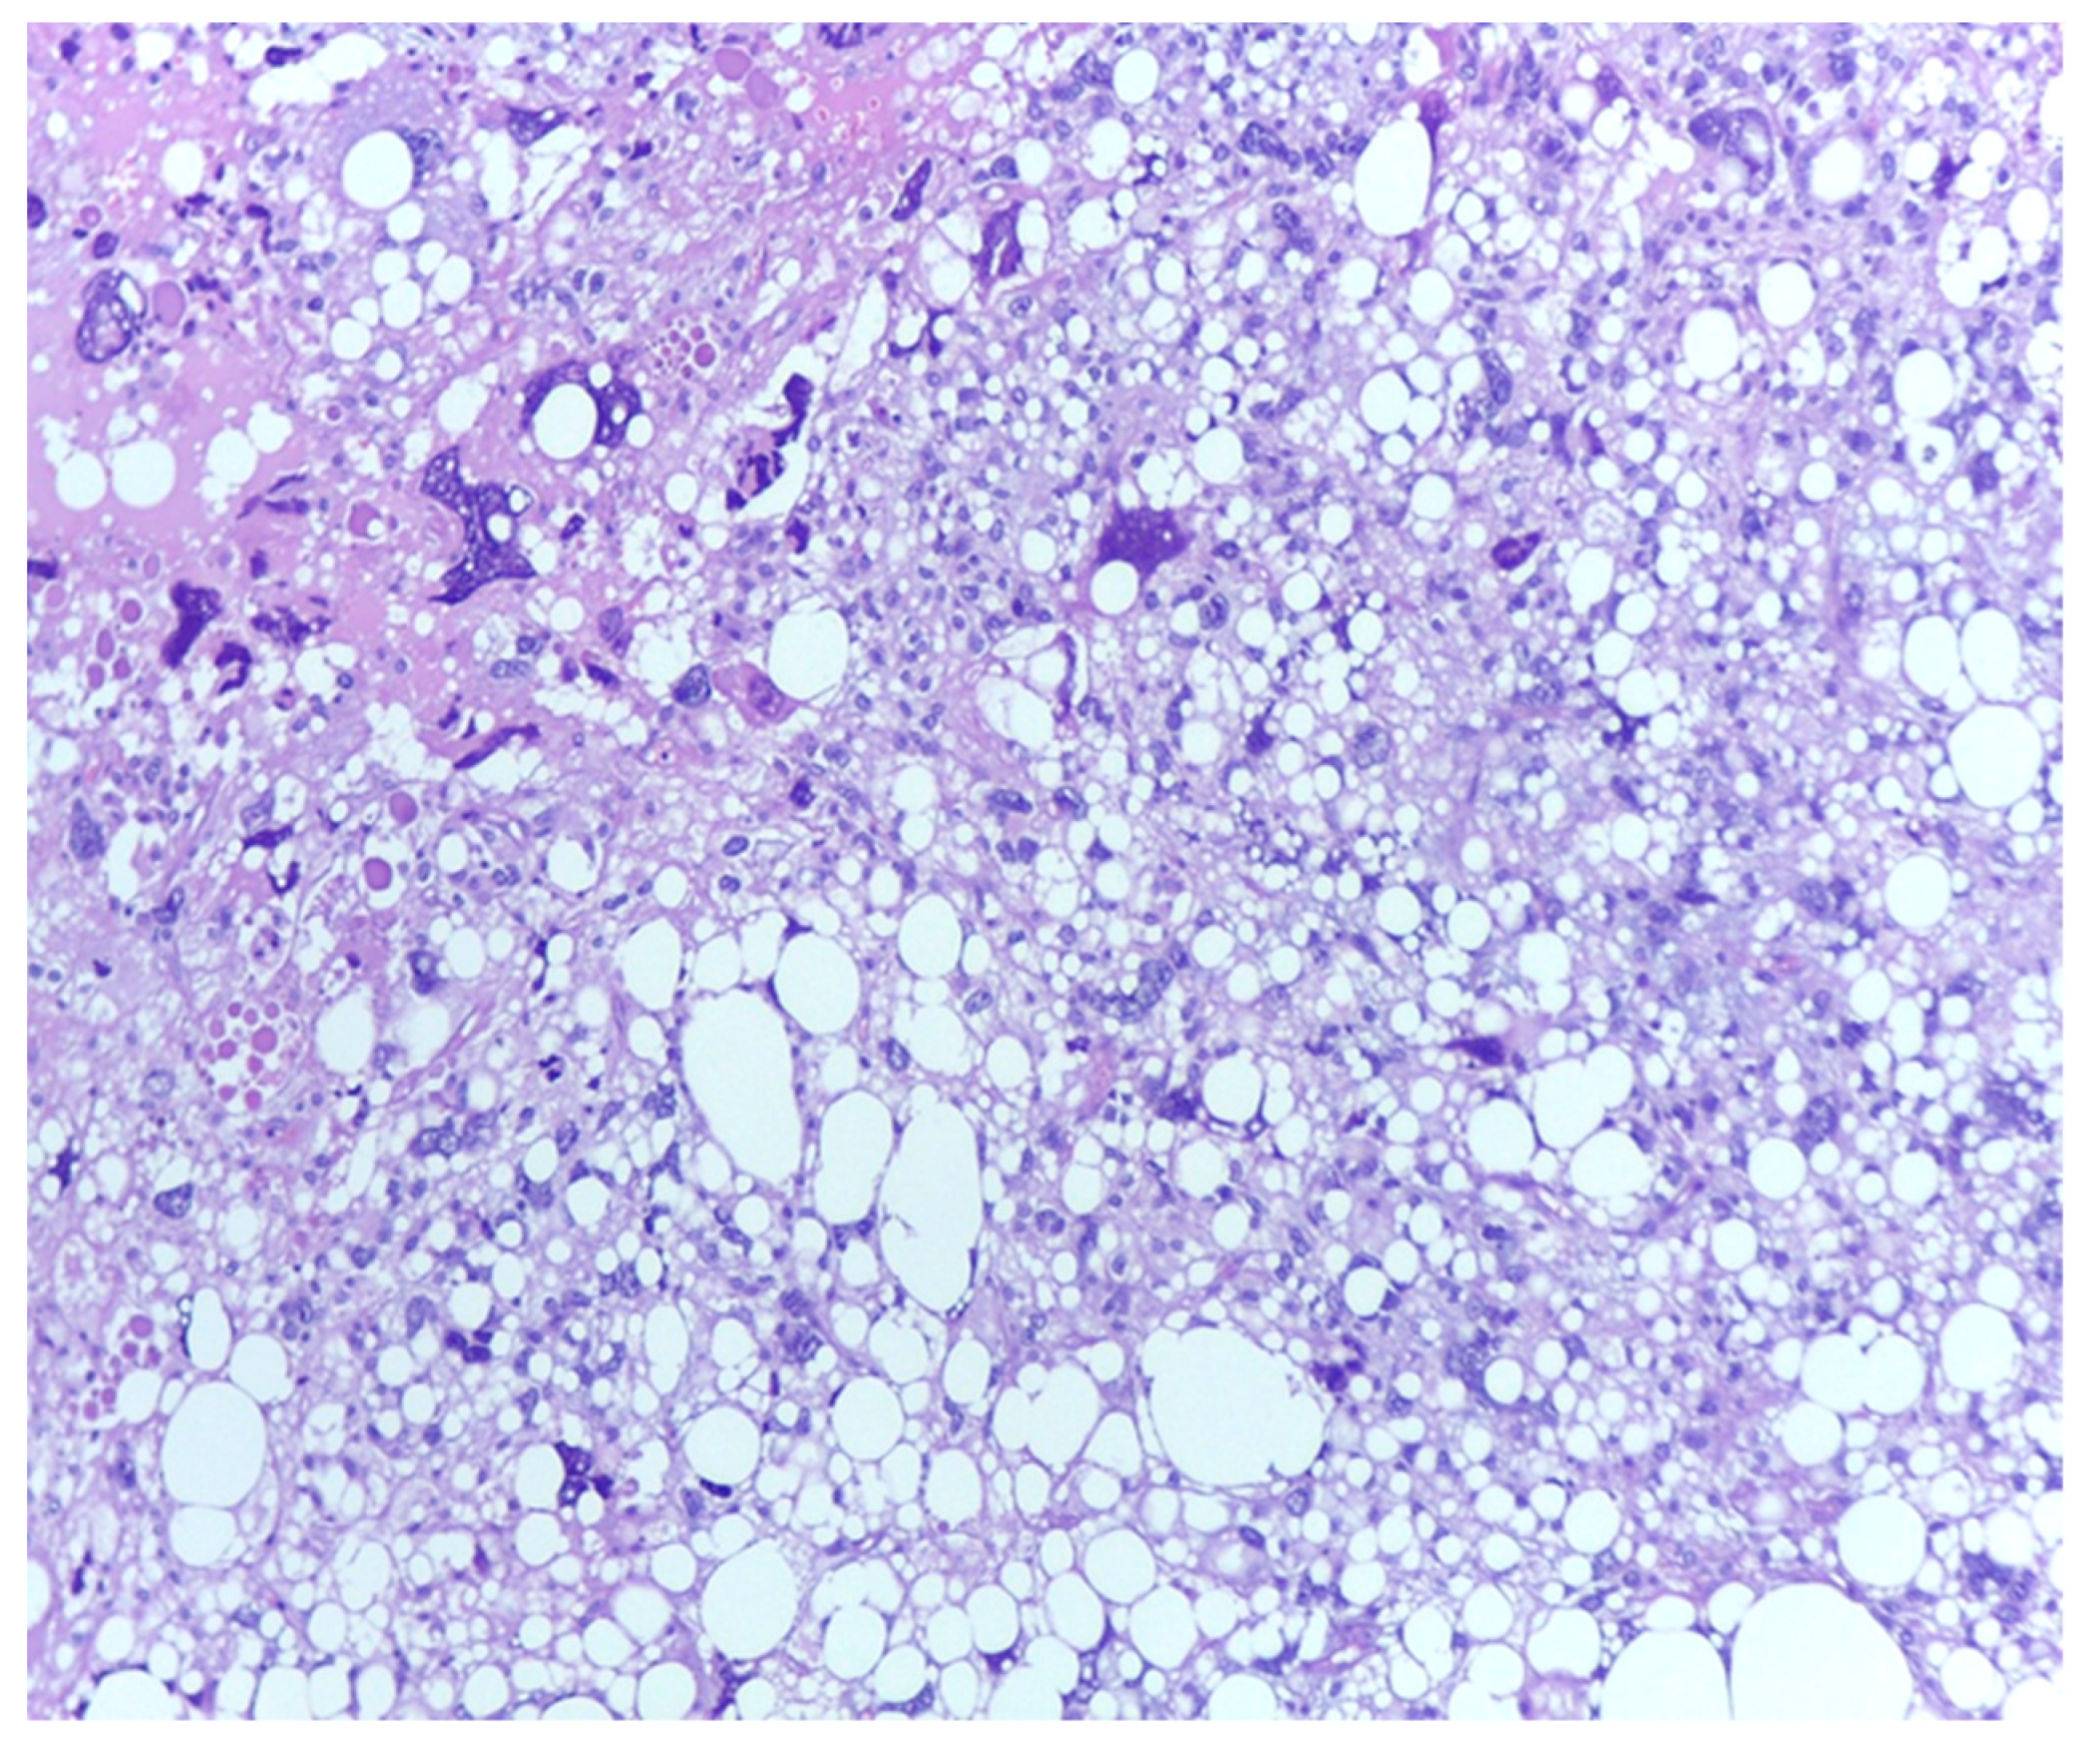

3.1. Tumor Grade